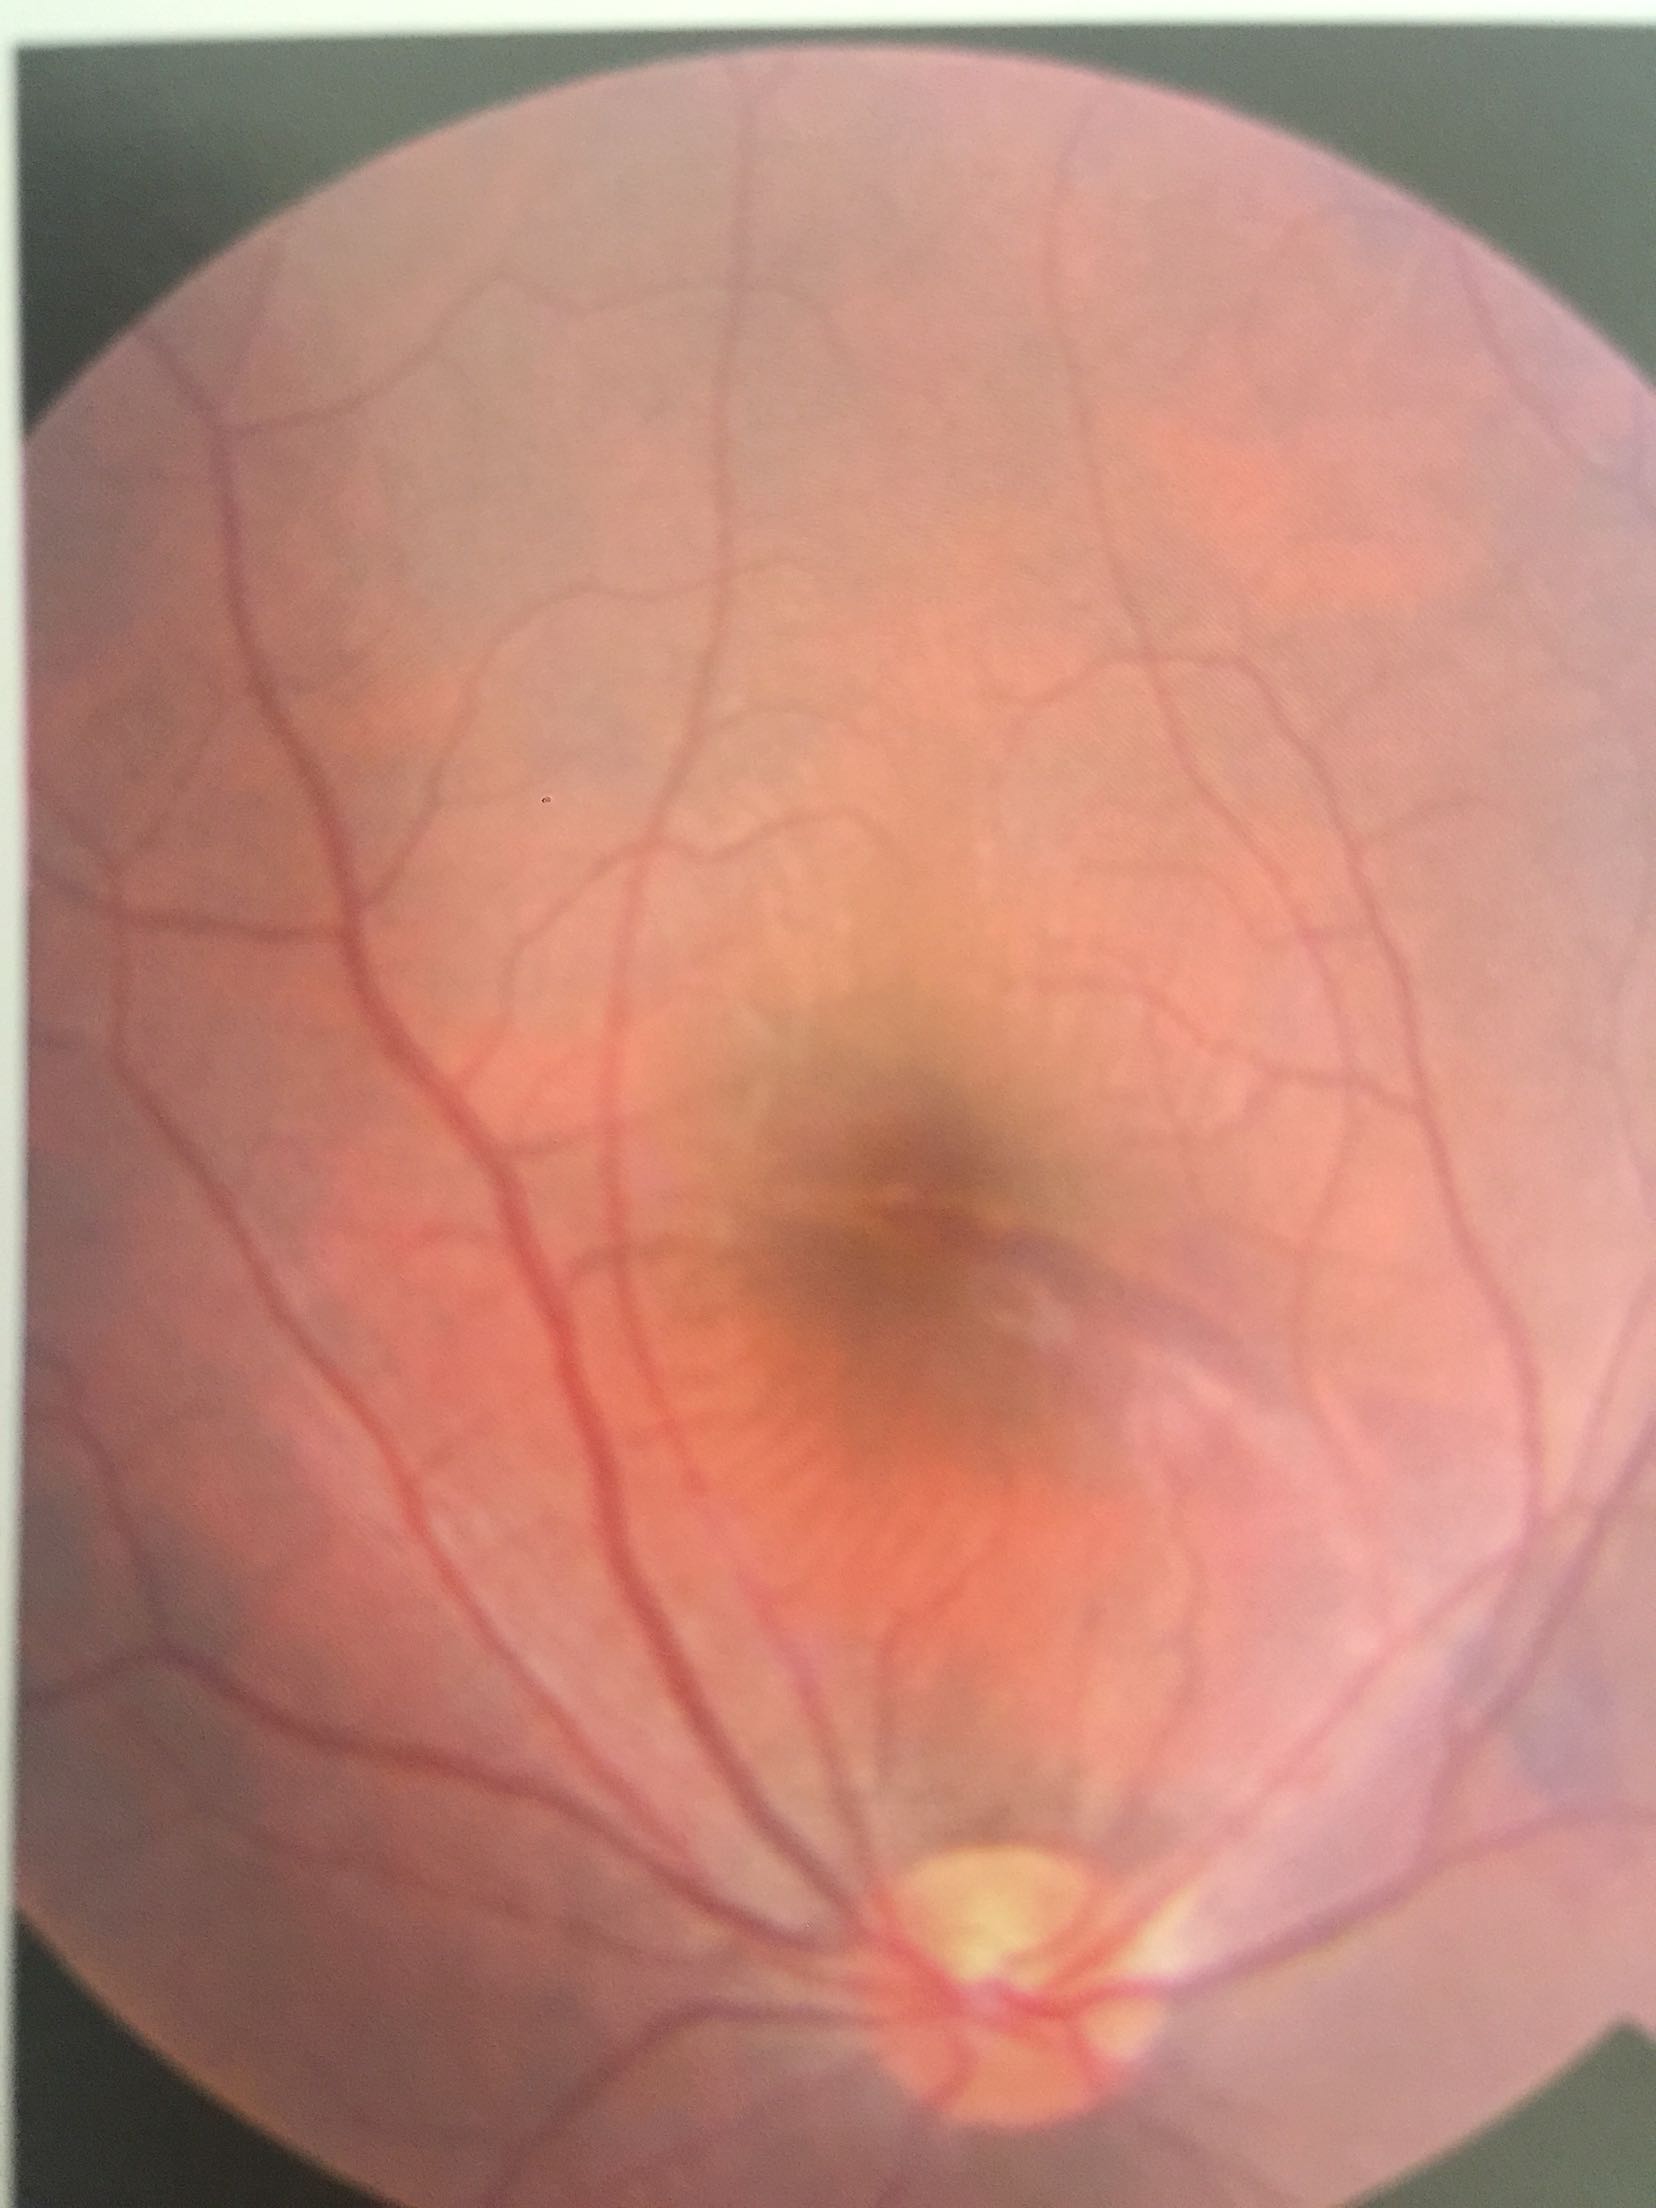

视力:右眼 0.2不能矫正 左眼1.0 眼压:16/19mmhg右眼结膜充血+角膜透明,前房3.0CT。晶体玻璃体透明。眼底视盘界清色可,颞上方血管弓与黄斑区之间可见一弧形脉络膜裂伤,裂伤处及其周围视网膜下可见浓厚出血。

右眼脉络膜裂伤 入院后给予甘露醇、Vc、联合中药治疗